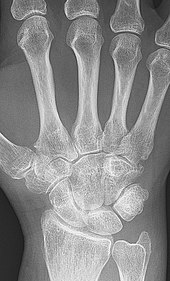

As the pathology progresses the inflammatory activity leads to tendon tethering and erosion and destruction of the joint surface, which impairs range of movement and leads to deformity. The fingers may suffer from almost any deformity depending on which joints are most involved. Specific deformities, which also occur in osteoarthritis, include ulnar deviation, boutonniere deformity (also "buttonhole deformity", flexion of proximal interphalangeal joint and extension of distal interphalangeal joint of the hand), swan neck deformity (hyperextension at proximal interphalangeal joint and flexion at distal interphalangeal joint) and "Z-thumb." "Z-thumb" or "Z-deformity" consists of hyperextension of the interphalangeal joint, fixed flexion and subluxation of the metacarpophalangeal joint and gives a "Z" appearance to the thumb.[18]: 1098  The hammer toe deformity may be seen. In the worst case, joints are known as arthritis mutilans due to the mutilating nature of the deformities.[22]

X-rays of the hands and feet are generally performed when many joints affected. In RA, there may be no changes in the early stages of the disease or the x-ray may show osteopenia near the joint, soft tissue swelling, and a smaller than normal joint space. As the disease advances, there may be bony erosions and subluxation. Other medical imaging techniques such as magnetic resonance imaging (MRI) and ultrasound are also used in RA.[22][55]